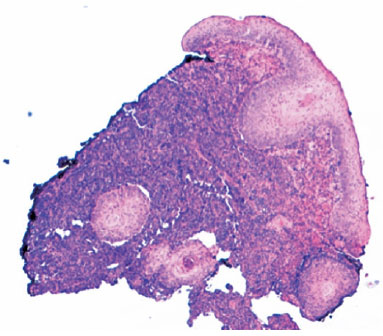

A CT scan revealed a circumscribed hyperdense eyelid mass, 15 × 7 mm in size, which did not compromise the eye; no orbital lesions were observed. An incisional biopsy of the lesion and a systemic extension study were performed. The anatomopathological study revealed pseudoepitheliomatous epidermal hyperplasia associated with giant atypical cells and dermic tumoral infiltrate that was positive for CD30 and CD45 and negative for CD20, CD3, CD2, CD5, CD8, CD7, AE1/AE3, S100, EMA, and ALK (Figure 3). The systemic extension study ruled out extracutaneous involvement. The diagnosis was multifocal primary cutaneous large cell anaplastic lymphoma, with a TNM stage of T3aN0M0.

07-fig03.jpg)